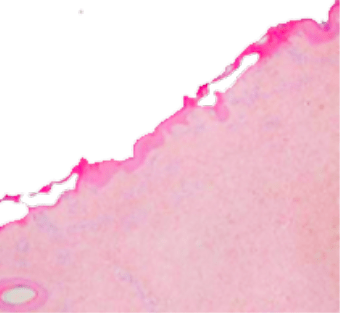

This energy is delivered through a narrow range of wavelengths, elevating the temperature in the targeted area, resulting in tissue evaporation or ablation. Ablative lasers effectively treat a broad range of skin conditions by removing all or only parts of the skin in a fractional manner. The body’s natural healing processes then drive the production of new elastin and collagen fibers, which help replace damaged skin with new and healthy tissue.

CO2 lasers produce light at a 10,600nm wavelength, which is absorbed by water molecules in the tissue. The laser energy heats up the water until it reaches a boiling point, causing the evaporation of the affected tissue. Some of the heat is absorbed by the tissue adjacent to the ablated target area, causing tissue coagulation which induces hemostasis (the cessation of bleeding) as well as thermal stimulation of deep skin layers, which induces fibroblast stimulation and neocollagenesis (the formation of new collagen).

The laser beam can also be transmitted through a scanner which is a device used to further control the delivery of energy. The scanner regulates the configuration of energy delivered onto the skin, which can range from covering the entire treatment area or just a fraction of it, leaving some areas of untreated skin that drive faster recovery (“fractional ablation”). The overall effect of ablation and coagulation, either full or fractional, is the removal of damaged skin and the stimulation of the body to replace it with newer, younger, and vibrant skin.